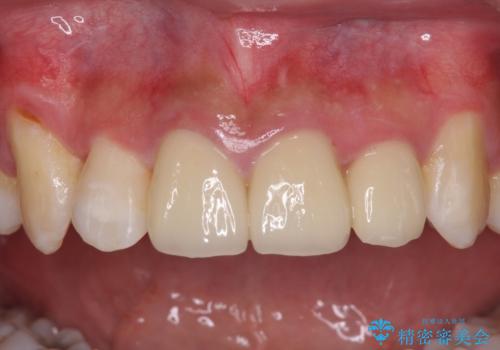

- 変色した保険の前歯のクラウンを交換したいとのことで来院された患者様です。

中心左側の歯はクラウンが装着されており、右側は神経組織が除去されて多少変色している状態でした。

右側の歯も将来的にもっと変色する可能性があるため、前歯2本をオールセラミッククラウンにて補綴治療を行うこととしました。

元々の歯の色が非常に白く、セラミッククラウンの色調を合わせるのに苦労しましたが、最終的に大変満足いただけるクラウンを装着することができました。